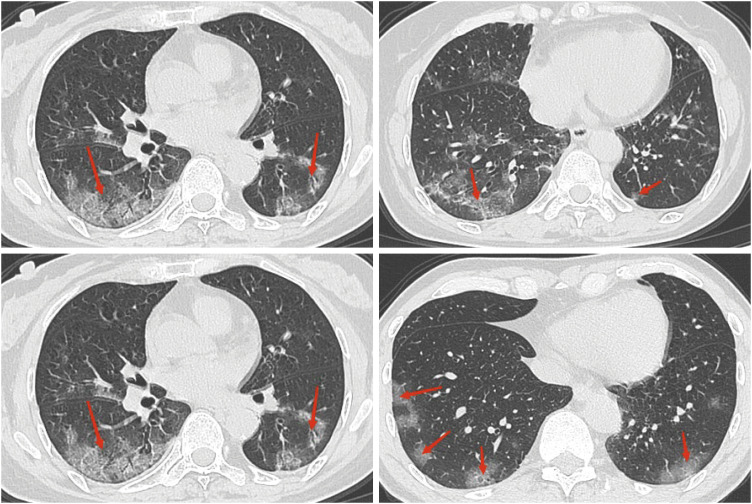

Purpose: During the major shift in China's policies on coronavirus disease 2019 (COVID-19), many residents will be infected with severe acute respiratory syndrome coronavirus 2 (SARS-CoV-2) over a short period, including a few patients with breast cancer undergoing neoadjuvant chemotherapy (NAC). Moreover, it is unknown whether this comorbidity affects the efficacy of NAC for breast cancer and the patient's psychological state and quality of life (QOL). This study aims to answer these questions.

Methods: The clinical data of 2,793 patients with breast cancer who received NAC at The Affiliated Hospital of Qingdao University were retrospectively collected. The infected and non-infected groups were divided according to whether they were infected with COVID-19 during NAC. Propensity score matching was used to reduce patient selection bias. The effectiveness, psychological well-being, and QOL of the two groups were compared.

Results: No discernible differences were observed in the pathological complete response rates (p = 0.307) and major histological responses rate (p = 0.398) between the infected and non-infected groups. Following the full course of NAC, the Functional Assessment of Cancer Treatment General (p < 0.001) and Functional Assessment of Cancer Therapy for Breast Cancer (p < 0.001) were lower in the infected group than the non-infected group, the Hospital Anxiety and Depression Scale (HADS) anxiety scale (p < 0.001) and HADS depression scale (p < 0.001) were considerably higher in the infected group than the non-infected group.

Conclusion: With timely treatment and effective medical management, SARS-CoV-2 does not appear to affect the efficacy of NAC; however, it can significantly affect the QOL of patients and increase their psychological distress. Therefore, in addition to a timely assessment of the efficacy of NAC, it is necessary to dynamically understand the patient's psychological state and QOL.